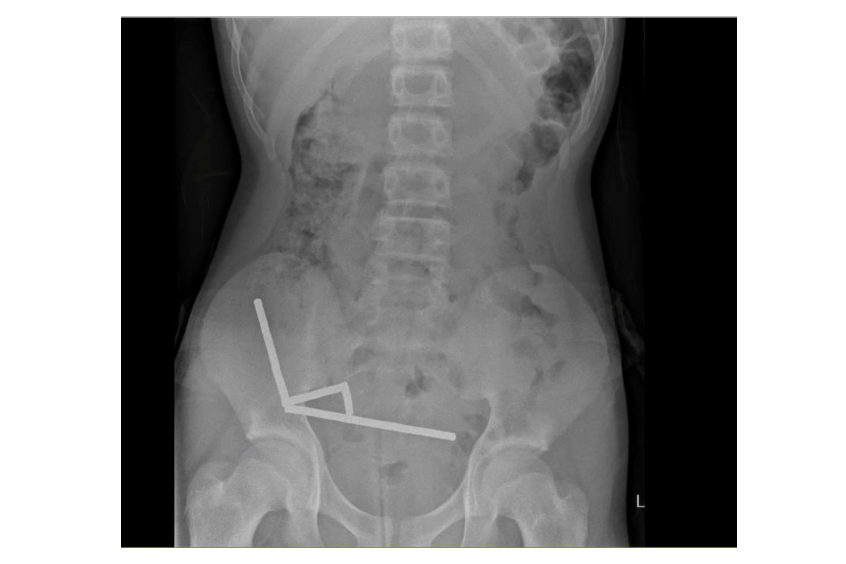

Hasil pemindaian menunjukkan magnet-magnet itu membentuk empat rantai panjang di dalam usus dan pangkal usus besar. Karena jumlah magnet yang banyak mengganggu hasil pemindaian, tim medis akhirnya memutuskan untuk melakukan operasi eksplorasi.